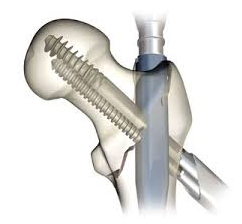

Many fractures require surgery to repair. Though surgery comes with its own risks, modern orthopedic techniques can lead to improved outcomes. The surgical technique used will depend on the nature of the specific fracture. Some of these techniques include:

» Metal plates may be screwed onto your broken bone to prevent it from moving and to promote healing

» Metal rod may be placed inside the center of a long bone to help reattach two ends of a fracture and to maintain alignment. This technique is called intramedullary fixation

» Pins and rods may be placed in your bones and continue outside your skin, where they can be attached to a metal cage. This technique is known as External fixation and allows for slight adjustments to be made to the orientation and position of a bone as it heals.